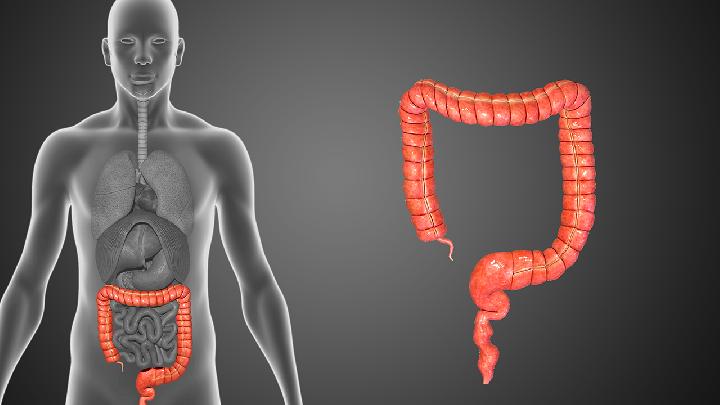

医院数字区 - 内科 - 消化内科 - 结肠炎 - 寿命

得了急性结肠炎能活多少年

秋季以及夏季是急性结肠炎高发季节,尤其是体质较差者,在饮食方面不注意或者是受到病毒以及细菌感染,很容易导致急性结肠炎发作。急性结肠炎在发作期间局部症状表现较为突出,会对患者自身健康造成较大影响,甚至有少部分患者认为该病影响生存期。那么,急性结肠炎能活多久? 一、急性结肠炎能活多少年 急性肠结肠炎具有发病急、易反复发作等特点,患者在患病期间会出现不同程度的腹痛、腹泻,有些患者甚至伴有发热、全身无力,四肢冰凉等其他症状。急性结肠炎属于良性病变,通过系统性治疗可以完全治愈,不会影响到患者生存期,患者可保持正常寿命。 1.一般治疗 若是急性结肠炎患者发病病程较短,局部症状较轻,选择一般治疗即可。一般治疗主要是补充患者液体、补充维生素以及钙质。对于腹泻、贫血发作者,可通过饮食以及肠胃外营养改善病情。 2.药物治疗 药物治疗是急性结肠炎根本性治疗方法,常用药物种类包括:抗感染类药物和激素类药物。常用的抗感染药物主要以水杨酸抑制剂更为常用,可以减轻恶心、呕吐、腹泻、腹痛等多种急性结肠炎症状,对于病情恢复有利;如果病情较为严重,腹泻次数过多,需要及时予以激素治疗,常用激素药物包括:肾上腺皮质激素、强地松等。这类药物可在短时间内减少的变次数缓解全身性症状,降低疾病复发率。但是选择药物治疗时,患者需要谨遵医嘱在医生指导下服用更为安全。如果私自服用药物或随意更改药物剂量,会影响到病情恢复,甚至会产生其他不良反应。 关于结肠炎的信息 胶原性结肠炎具体诱因较多,一般认为该病发生主要与生活与饮食因素、感染性因素有关。另外,遗传性因素和免疫功能低下等其他因素,也是导致该病发作的常见诱因,同样不可忽视。为避免该病发作,在生活中要远离这些诱发性因素。  慢性结肠炎是很常见的一种疾病了,给患者带来的危害是相当大的,但是很多人在患上了慢性结肠炎都不知道慢性结肠炎的病因,那么慢性结肠炎的病因是什么呢?接下来我们就一起来看看慢性结肠炎的病因。  对于结肠炎,很多患者表态吃药就缓解,一停药就复发,这是没有找到正确治疗结肠炎的方法的缘故。下面,就为大家介绍结肠炎常复发的原因:  结肠炎发生在人们的结肠的部位,这种病粗要及时的进行治疗,不能够延误,这种疾病的很大特点就是容易反复出现,给人们的生活带来了不可磨灭的痛苦,生活中我们都要有防患的意识,那么我们该怎么断定是不是结肠炎呢?下面就看看专家的讲解。  结肠炎是我们常见的一种疾病了,结肠炎给患者带来的伤害也是非常大的,所以对于结肠炎的饮食我们也要掌握理解,那么结肠炎的饮食有哪些注意事项呢?接下来我们就请专家来为大家介绍有关结肠炎的饮食注意事项。  随着患有结肠炎的人数越来越多,人们也渐渐对结肠癌炎所重视,结肠炎的治疗也就成为人们比较关注的话题,那么结肠炎如何治疗呢?接下来我们来一起了解下吧。  慢性结肠炎能生小孩吗?当溃疡性结肠炎处在活动期时,怀孕常常使结肠炎症状加重,尤以妊娠头3个月为甚,少数病人可好转。当溃疡性结肠炎达到缓解期时,百分之二十五至五十二病人在妊娠头3个月之内复发较多,在产后期复发较少;自发性流产率较高;引产以后有的病人出现病严重迁延。  ,结肠炎发病率比较高,患者要注意这个疾病,一旦出现结肠炎应该正确的诊断治疗。下面就针对这一问题做详细介绍。由于正确的诊断结肠炎,可以帮助正确的治疗结肠炎,帮助患者早日康复,具体结肠炎的诊断方法有:  慢性结肠炎是一种比较常见的疾病,相信大多数人群都能够知道这种疾病,但是,对于这种疾病真正能够做到了解的人却是很少,包括那些曾经是结肠炎患者的人群,其实这是非常不对的,对于常见性疾病,人群应该做到对其有一定的了解,重点是其病因,以及症状表现:  结肠炎的发生会有便秘、腹部疼痛等难受的现象,每个结肠炎患者都想彻底治愈、尽快治愈自己的疾病,可以却不知道怎么去选择结肠炎的治疗方法,那么、如何更好更快改善结肠炎呢?我们一起看下以下相关介绍。 |